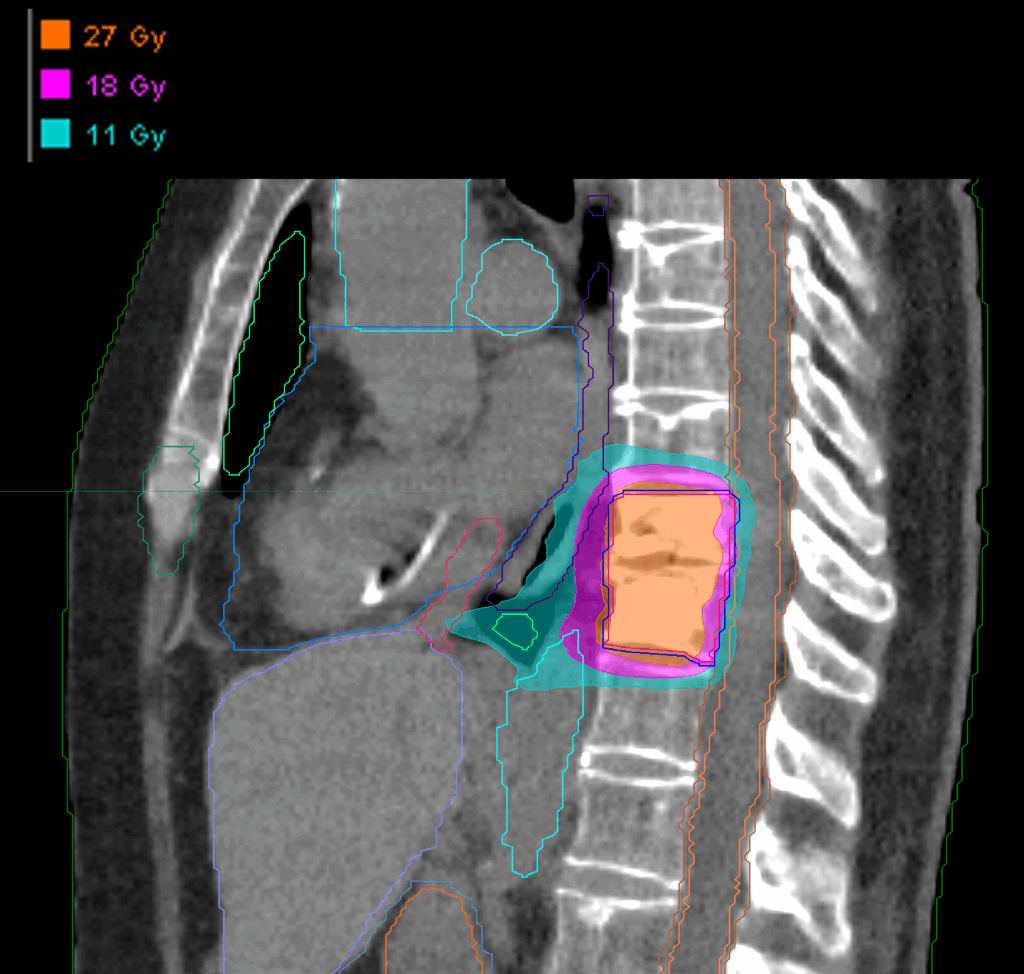

Treatment Plan Images

Fractionation

27 Gy in 3 fractions

Dose Distributions

- Prescription to the

75.6% isodose line - Max. dose 35.71 Gy

New Conformality Index (nCI)

nCi = 1.33